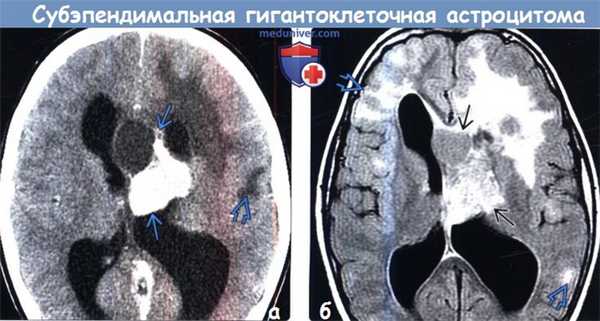

Обратите внимание на четкие края опухоли и кортикальные туберсы. Несмотря на экстренное вентрикулярное шунтирование, декомпрессия желудочков не была успешной. (а) КT с контрастированием, аксиальный срез: у пациента с ТСК определяется крупное частично кальцифицированное объемное образование, обтурирующее отверстие Монро. Обратите внимание на гиподенсный участок поражения в подлежащем кортикальному туберсу белом веществе.

(б) MPT, FLAIR, аксиальный срез: у того же пациента определяется, что выявленное образование имеет неоднородно гиперинтенсивный сигнал. Обратите внимание на кортикальные туберсы и очаги гиперинтенсивного сигнала, расположенные в субкортикальном белом веществе. При операции была выявлена СГКА.

(а) КT с контрастированием, аксиальный срез: у пациента с ТСК определяется крупное частично кальцифицированное объемное образование, обтурирующее отверстие Монро. Обратите внимание на гиподенсный участок поражения в подлежащем кортикальному туберсу белом веществе.